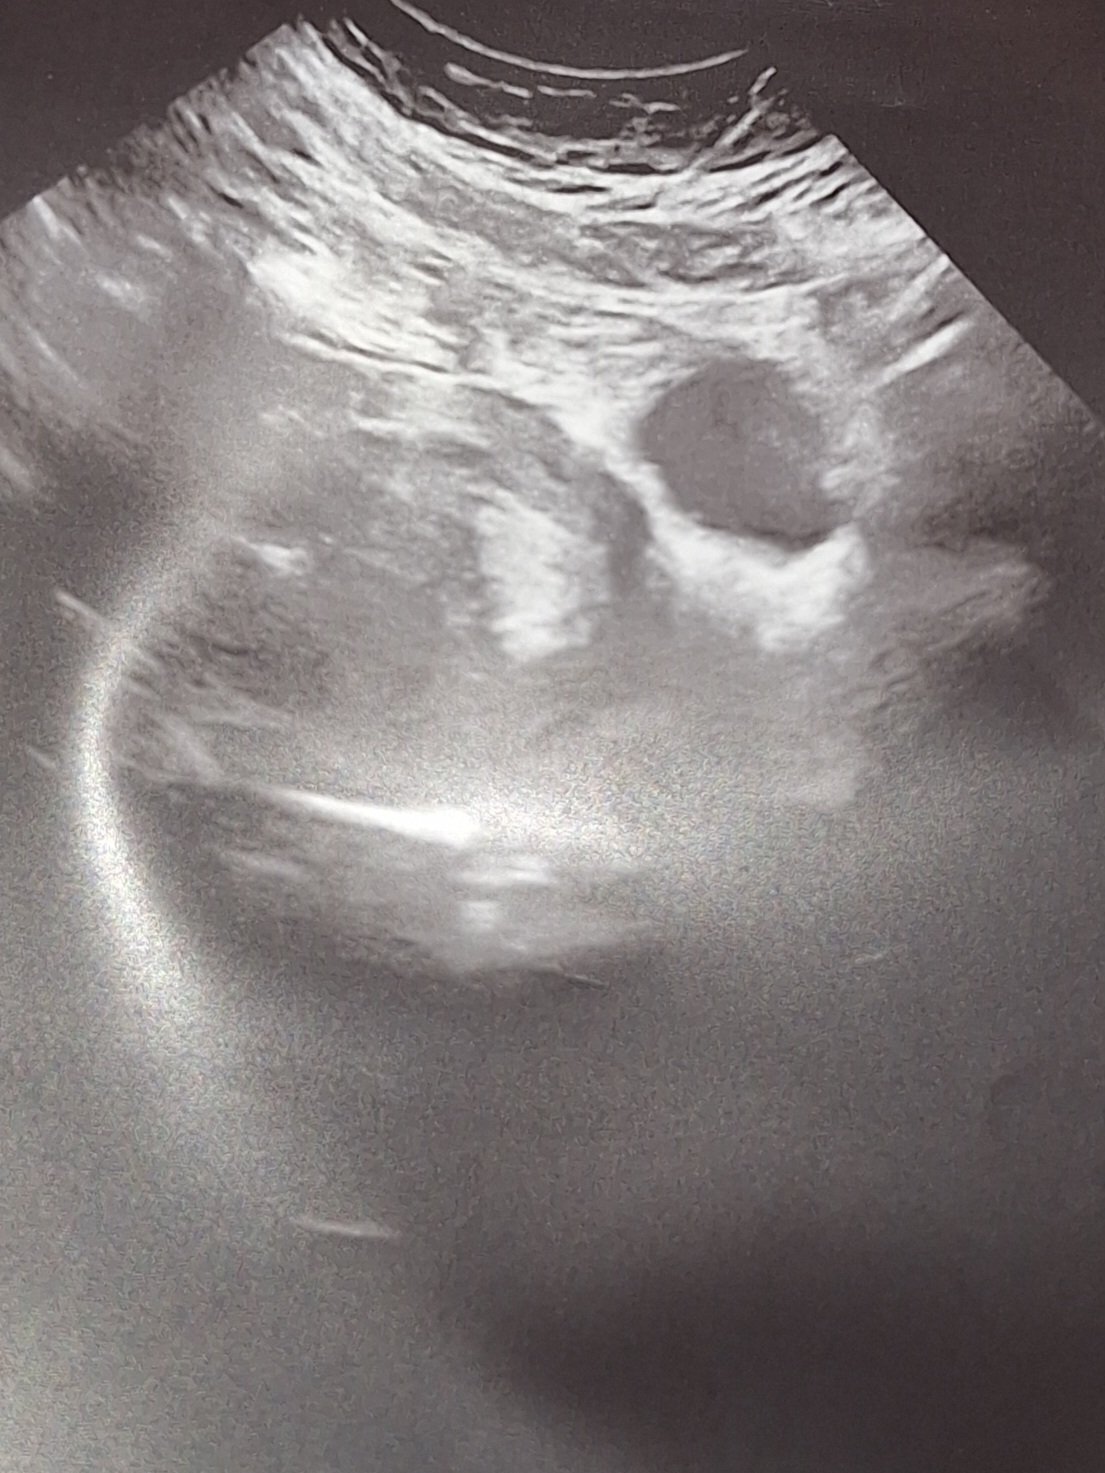

Какво представляват белите точки в плодния сак на ехографската снимка?